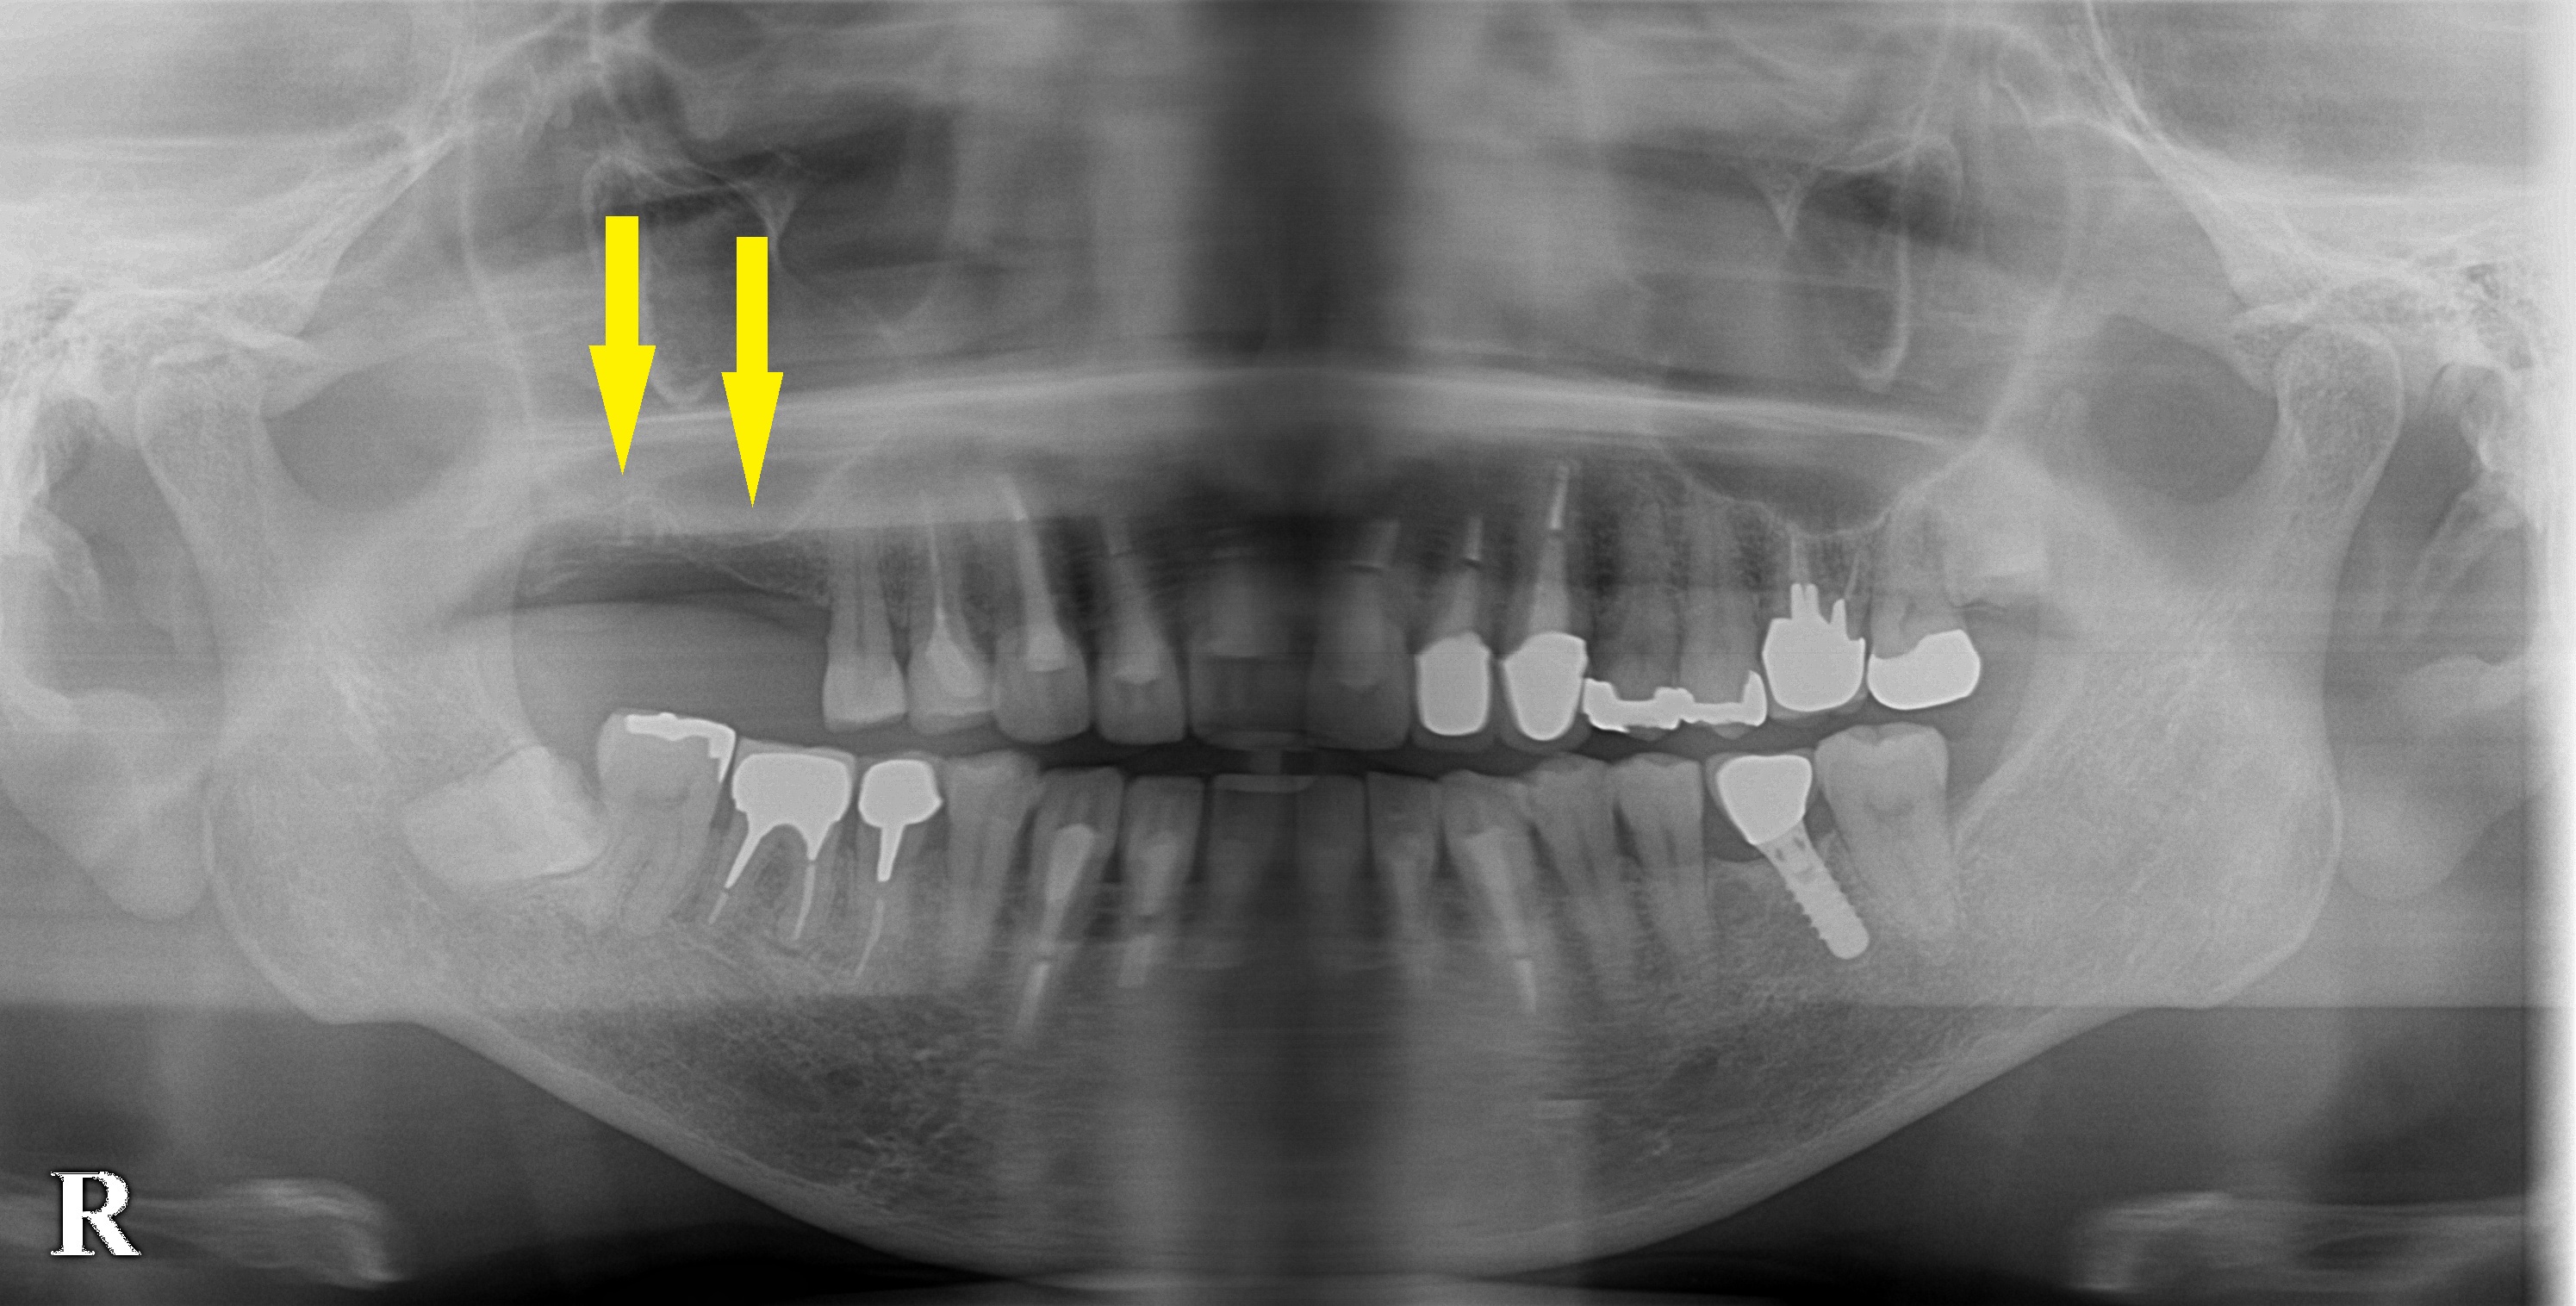

患者様は名古屋在住の60代男性。

右上顎の大臼歯が大きく動揺し、痛みも強かったために抜歯となった患者様です。

以前、左下顎のインプラント治療を行い、大変ご満足いただいていてここに紹介させていただいた患者様です。

右上顎も、インプラントにしたいとのご希望だったのですが、骨が非常に薄いために、骨造成が必要であると説明させていただきました。

それでもインプラント治療を希望されたので、本日、まずは、サイナスリフトという骨造成術を行ないました。